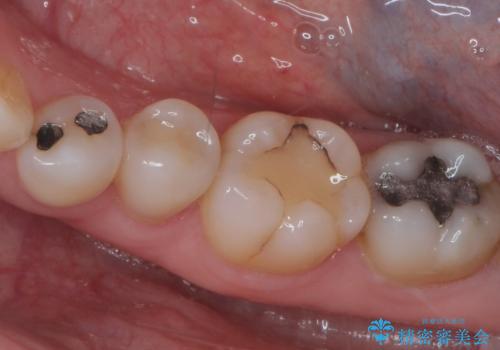

前歯の虫歯 つぎはぎの歯をセラミックに

- 矯正治療後に、前歯の樹脂の詰め物のやりかえを提案していましたが、治療は当時行いませんでした。

その後3年間来院がなく、その間に前歯の虫歯の進行があり、治療を行いました。

やはり、樹脂で虫食い状になってしまうと虫歯が進行しやすくなっているためクラウンがおすすめです。